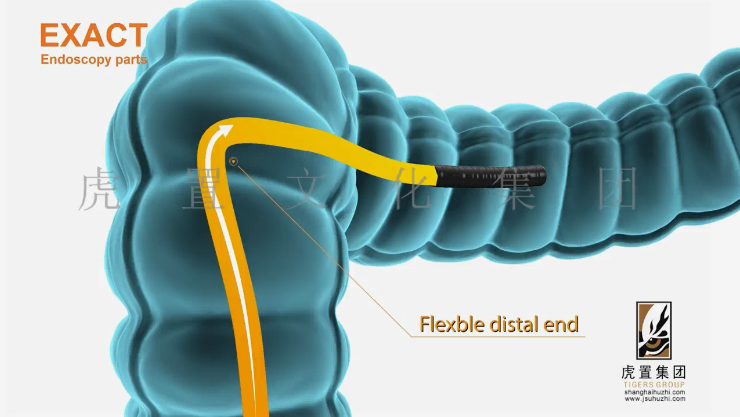

特效是提升三维动画工业机械设备表现力的重要手段。在合成阶段,可添加粒子特效模拟设备运行时的火花、烟雾,或使用光效增强金属表面的高光质感。例如,在展示激光切割设备的动画中,通过粒子特效制作激光束切割材料时产生的飞溅火花,配合光线追踪特效,呈现激光的高亮与穿透效果,让画面更具真实感和震撼力。

此外,动态模糊特效可强化设备运动的速度感。当机械臂快速抓取工件时,添加动态模糊能模拟人眼对高速运动物体的视觉效果,使动作更加流畅自然。但特效的使用需适度,避免因过度堆砌导致画面杂乱,掩盖设备本身的展示重点。

致力于:全案设计、展馆展厅、三维动画、卡通动漫、影视广告、3D效果图等综合服务,设计包括:建筑设计、景观设计、规划设计、展馆设计、室内设计、 BIM设计;展示包括:三维动画、全息展示、影视广告、数字展馆、二维动漫、3D仿真效果图、VR&AR等;施工包括:展馆展厅、室内装饰、幕墙工程、亮化工程。